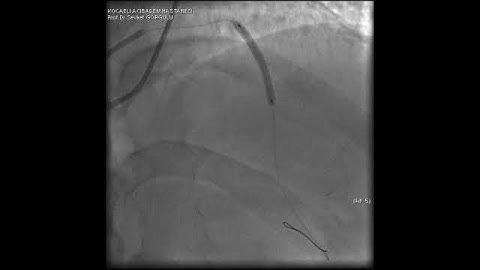

Microcatheter Tip Fracture During LAD CTO PCI: A Complication Video 3